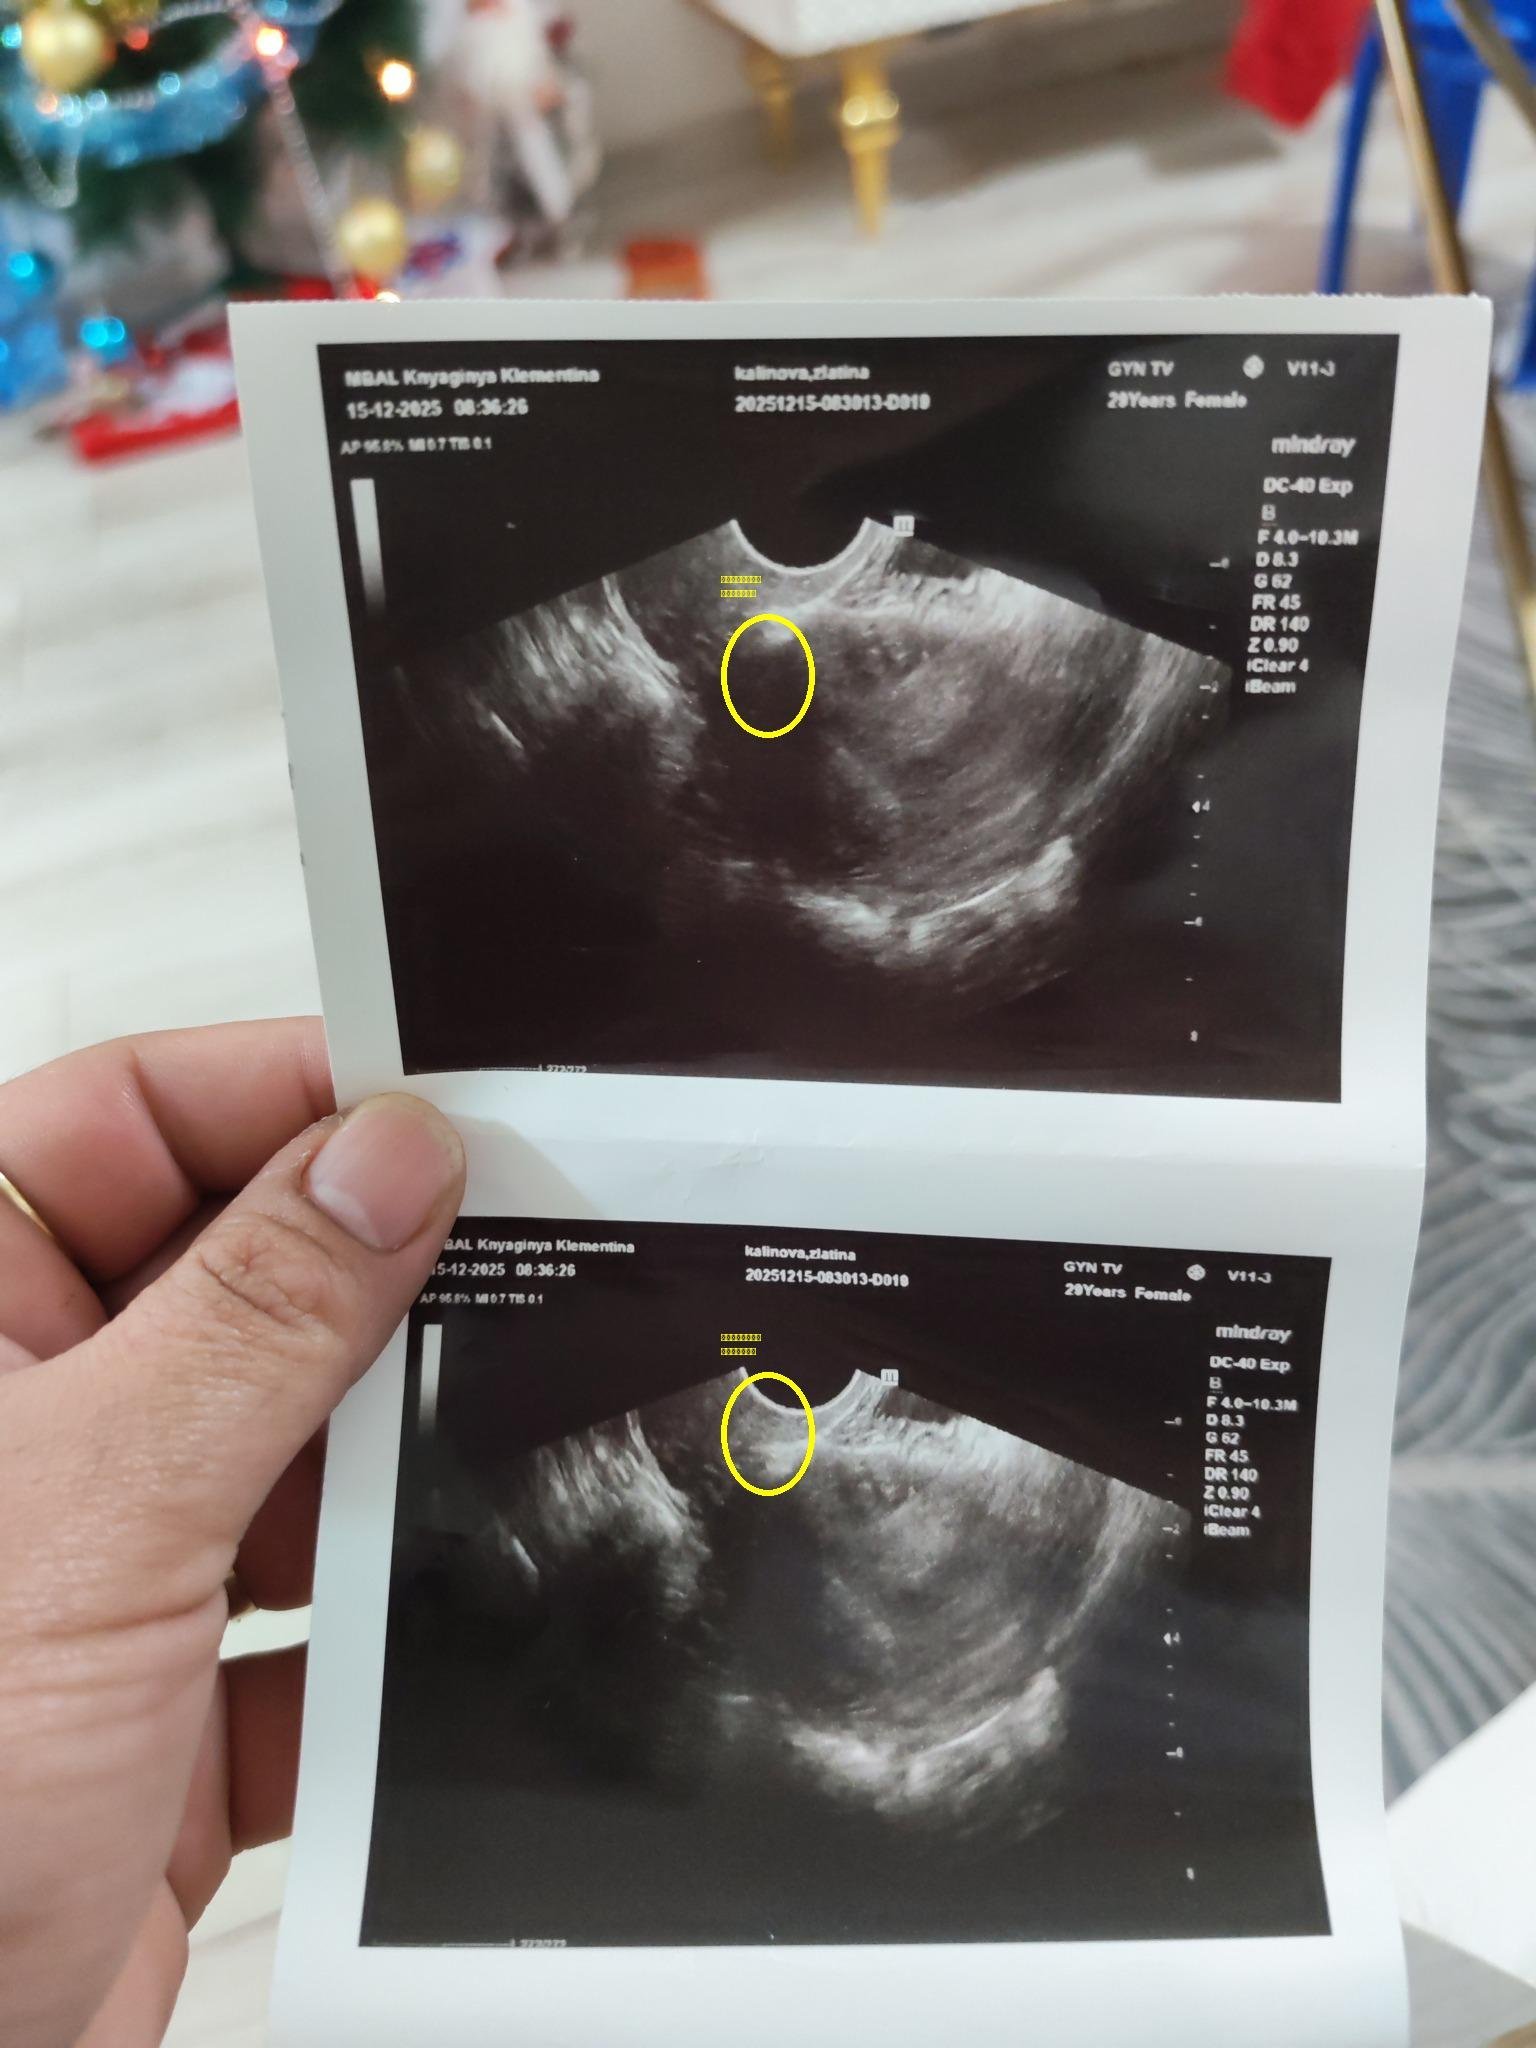

Към днешна дата и при тази стойност следва да има сакче с ясно изразена ембрионална структура.

Ето такова нещо (при вглеждане се вижда ембрионалната маса ниско долу в сакчето - това е снимка на най-малкият ми син на денят, в който е днес Злати):

Това са снимки от вчерашният преглед. Не го очетра, като плоден сак, защото било с неправилна форма. Идея си нямате колко лекари ме гледат. И реших да си дам почивка няколко дни, защото психически ще откача

- ЧХГ НЕ нараства правилно. Според измерванията на 8, 12 и 15.12 се удвоява средно за около 150 часа. Нормата за удвояване е до 72 часа.

-  в 5+3/5+4 трябва да се вижда вътрематочна бременност. Аз на последните снимки не виждам нищо такова. Така изглеждаше моята двуплоднна бременност в 5+3. Не можеш да го сбъркаш:

Права е 2402. Нарастването е неправилно и щом има сакче, но с неправилна форма, вероятно се касае за неправилно развитие или мисед.

Неправилната форма често се дължи на липса на ембрионална структура